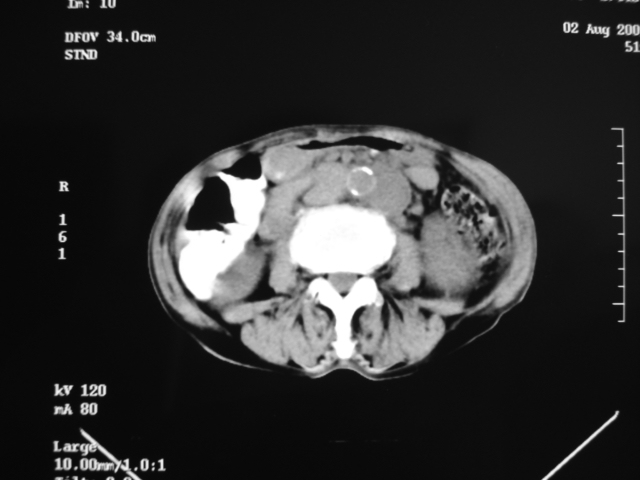

同事奶奶,73岁,腹痛一年,夜晚较重,潜血+++,拒绝增强,考虑左肾ca并腹膜后转移;请各位老师帮忙看看,谢谢!

左肾癌侵及输尿管上段,腹膜后多发淋巴结转移,脾脏钙化灶。至于潜血+++,要考虑消化道病变,本次ct片肠腔未见明显异常。

1)考虑左肾癌侵犯肾盂并腹膜后淋巴结转移。2)脾脏钙化灶。

定位像见上肺野也很糟糕,支持7楼。